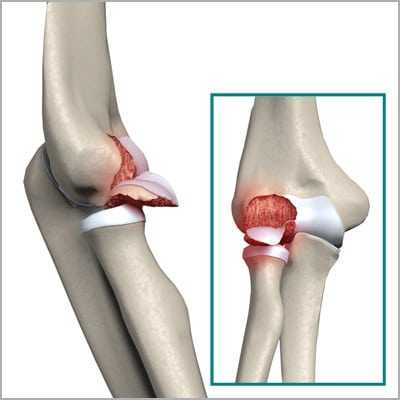

Перелом шейки и головки лучевой кости